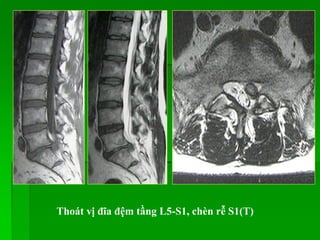

Thoát vị đĩa đệm tầng L5-S1, chèn rễ S1(T)

Thoát vị đĩađệm tầng L5-S1, chèn rễ S1(T)